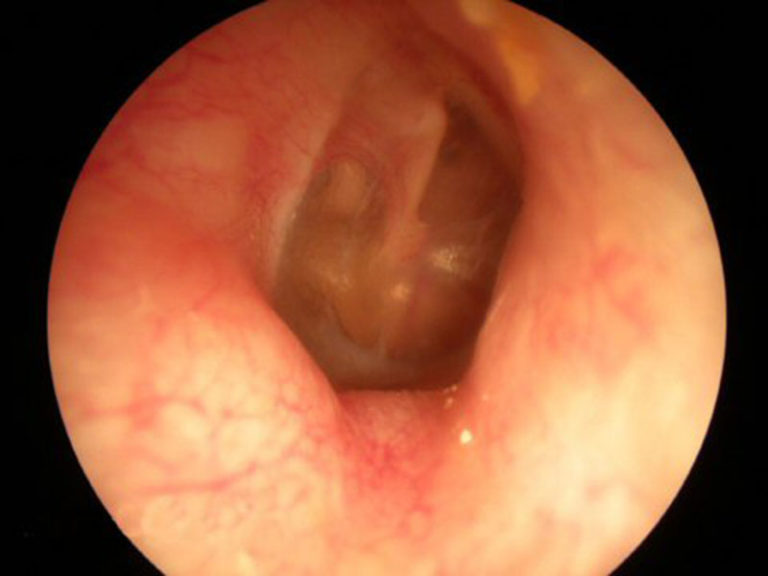

Часто причиной появления шума в ушах являются воспалительные процессы, в том числе секреторный отит. Это воспаление характеризуется тем, что серозная жидкость и другие микроэлементы, а также бактерии и микробы, часто накапливаются за ушной перепонкой, оказывая давление на барабанную перепонку. Это может привести не только к развитию патогенной микрофлоры в ушах, но и к разрыву перепонки.

Наиболее частой причиной появления плеска в ушах является секреторный отит.

При накоплении экссудата в среднем ухе за барабанной перепонкой или во внутренней полости органа происходит раздражение элементов цепочки звукопередачи. Однако важно понимать, что отсутствие боли не гарантирует нормального состояния. Как правило, это скорее указывает на развитие осложнений, таких как хроническое воспаление.

Аномалии звучания, подобные этим, обычно наблюдаются в начальной стадии воспалительных заболеваний. В этот период естественные выделения начинают накапливаться из-за блокировки дренажной функции евстахиевой трубы. Размножение микроорганизмов приводит к образованию сывороточных и гнойных выделений. При частичном заполнении среднего уха жидкость может перемещаться, вызывая соответствующие звуки. При полном заполнении возникает ощущение заложенности, давления и боли. Выделения могут проникать в другие части уха и быть удалены путем прокола барабанной перепонки или ее парацентеза.